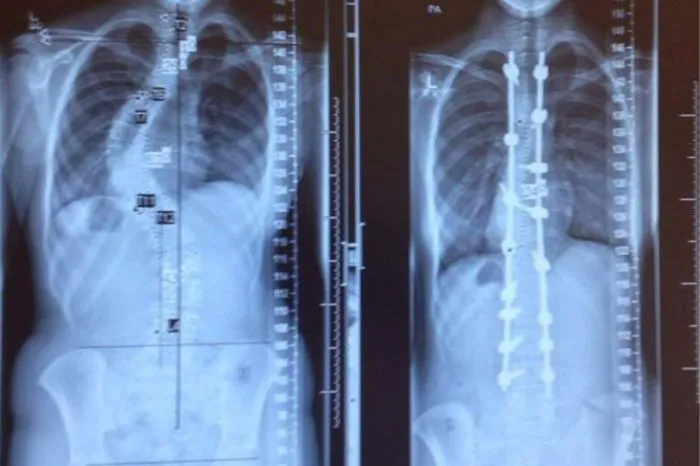

12. Позвоночник до и после лечения сколиоза. Обычно хирургическое вмешательство и установка конструкции проводится только в том случае, если искривление превышает 50%